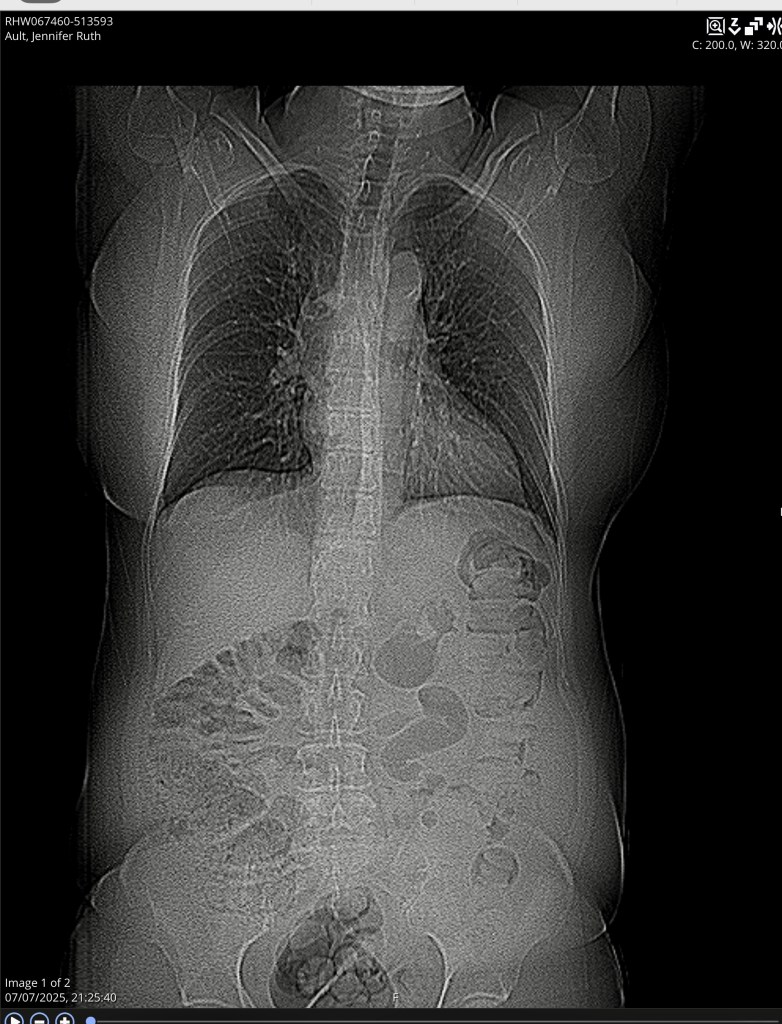

In July 2025 I fell and fractured my spine . This was a shock and caused a lot of pain; which I still have. It has meant adjusting and like when I lost my hearing; emotionally I was effected.

The X-rays that were taken show the compression fracture clearly. I was struck by the detail of the bone and organs internally show how inter connected the spinal structure is with the other parts of our body. Each vertebrae links to a different part of our body. T12 is next to the 12th posterior rib and followed by L1 the first vertebrae of the lumbar spine.